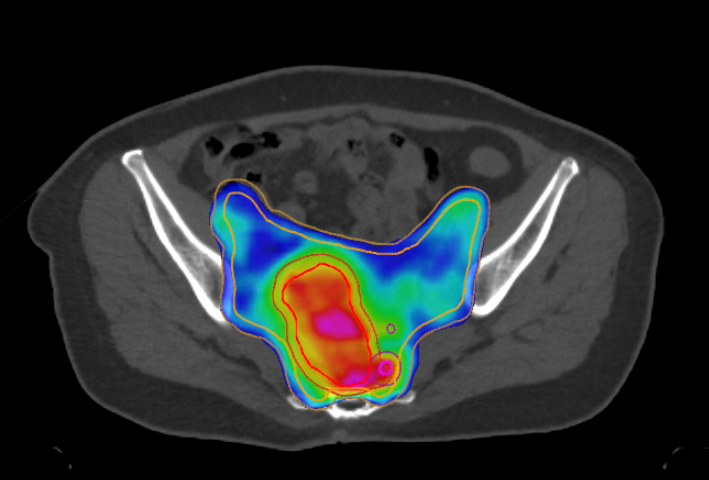

60岁的李女士(化名)直肠癌术后2年,复查时发现右肺新发病灶。得知这个消息她一度陷入绝望。手术做了,化疗也坚持完成了,癌症还是卷土重来了……抱着一丝希望,李女士来到和祐医院就诊。经过和祐医院肿瘤医学中心多学科团队(MDT)的深度会诊,放疗科、肿瘤内科、外科、影像科专家共同研判后,给出了一个关键结论:这并非广泛扩散的"全面战争",而是转移灶数量极为有限的"寡转移"状态!

在直肠癌治疗的今天,放疗、化疗与手术已不再是孤立存在的治疗方式,而是共同构成了一套高度协同、讲究时机与顺序的“综合诊治策略”。和祐肿瘤医学中心近期完成的一例成功病例,正体现了这种医学理念背后的力量。